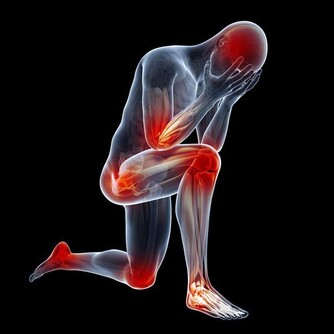

血管斷了,魔鬼就在你的身體里安家了。我就是在第一次手術時被結紮了左側主靜脈。從此,我的左側胳膊就在也沒有抽出來過血。同時由於主靜脈的結紮,使全身的血液流通不暢,經常偏頭痛,結紮一側的體溫略低。這種溫差別人是感覺不到的,體溫計也不起作用,但是自己的感覺卻很明顯,因為左腿永遠比右腿涼。此時的我,感覺和魔鬼把我的身體從中間豎著分開了,右邊的歸我管,左邊的歸魔鬼管。

這種感覺在偏頭痛的時候特別明顯。我都恨不得拿把鋸把自己從中間鋸開。還有一次,因為我的右側卵巢有個小瘤,做了腹腔鏡的小手術,手術後右側很快就恢復了,而左側就因為血液的流通不好,落下了盆腔炎,花了整整一年才治好。

第二次的手術,將我的頭頸靜脈結紮了,所以,手術後,我的左耳和左邊半個頭都是麻木的,沒有知覺了——我的左半啦都交給魔鬼了。很多病友也都說頭皮是麻的。將來老了,結紮的這一側的血栓的機率也會比另一側高。所以大家要多加註意。

甲狀旁腺被拿掉了,必然影響全身鈣質的吸收,就要終生補鈣。長期缺鈣對身體的影響是巨大的,甲狀旁腺的功能是強大的,損失了它,代價是巨大的。短時間的血鈣低身體就會發麻,抽搐,長期的缺鈣會導致骨密度降低,引起骨質疏鬆,你就是那個一碰就碎的玻璃人。輕輕的一個跟頭,就能斷了胳膊腿。

萬幸我的個子是長起來了,165cm,算是中等個了。由於無知,上大學時偷偷停了半年的藥,我就是不想終生服藥,想看看停藥有什麼不行的。半年後,甲減的症狀越來越明顯了,出現了思維跟不上的情況,明顯反應遲鈍。更壞的結果很快就來了,在一次體育跳遠課上輕輕的一跳,就跳成了左腿脛骨粉碎性骨折,打了一個月石膏。後來經過一年的康復鍛煉,腿才又恢復了。我從骨折後有開始恢復服甲狀腺素片了。甲狀腺癌復發有可能是從那時開始的。